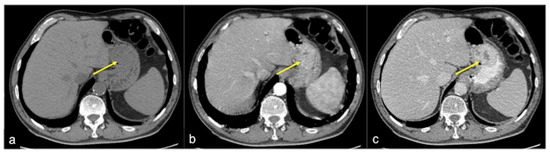

| Angiodysplasia (Figure 5 and Figure 34) | Asymptomatic or bleeding. | Small hyperdense nodules within the intestinal wall, best defined in the portal phase of the study. |

| Low flow rate of contrast media administration | Rigorous CTA/DECTA examination technique; post-processing reconstructions (Figure 11 and Figure 14) |

| Low-flow bleeding or reduced cardiac function/hypovolaemic or septic shock etc. | CTA/DECTA late venous phase; post-processing reconstruction (Figure 4 and Figure 9) |